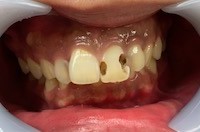

虫歯の治療では、虫歯菌に侵された部分をしっかり削り取らなくてはなりません。

もし虫歯が浅ければ、削る範囲も小さくすみます。しかし虫歯が深く進行していた場合、どうしても「神経の近くまで削る」必要が出てきます。

歯の中には「象牙質」という層があり、そのさらに奥に「歯髄(神経)」があります。象牙質には無数の細い管(象牙細管)が走っていて、外部からの刺激がこの管を通って神経に伝わります。虫歯が深く、神経近くまで削った場合には、この象牙細管を通じて冷たい刺激や熱い刺激が神経に届きやすくなり、結果として 治療後の「しみる症状」 が出やすいのです。